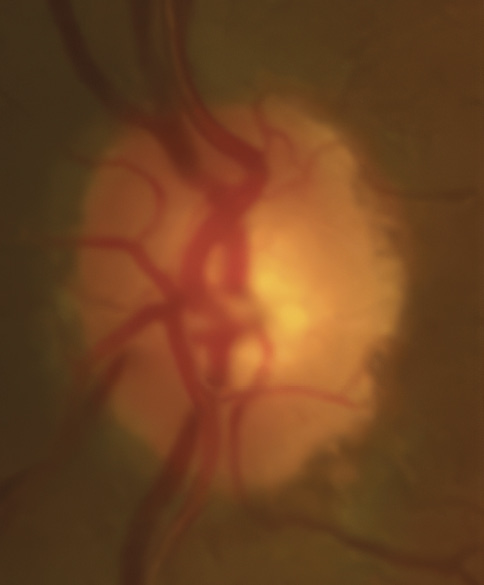

Bild 7: Fall 2 – (a) Sehnervenkopf OD, (b) Sehnervenkopf OS

A 46-year-old African American male presents for glaucoma quarterly monitoring. Medical history is positive for hypertension controlled with 50 mg hydrochlorothiazide and reports no diagnosis of diabetes mellitus or known drug allergies. Ocular history is positive for progressive myopia bilaterally and pigment dispersion syndrome converting to pigmentary glaucoma right eye mild, left eye moderate with treatment initiated in September of 2016. The pigmentary glaucoma was treated with 0.005% latanoprost in both eyes every evening. There was positive family history of glaucoma (patient’s father). Best corrected visual acuity was measured at 20/25 in each eye. Pupillary assessment revealed a stable 1+ afferent pupillary defect in the left eye. Confrontation fields were full to finger count in the right eye and superonasal constriction in the left eye. Extraocular motilities were full with no restrictions or report of diplopia in both eyes. Slit lamp examination is remarkable for a Krukenberg spindle (Figure 4) bilaterally and a Zentmeyer line (Figure 5) in the left eye. Intraocular pressures at 3:30 pm via GAT measured 18 mmHg right eye, 23 mmHg left eye. Gonioscopy was performed and revealed open angles to ciliary body with a concave iris configuration and 4+ trabecular meshwork pigmentation (Figure 6) and the posterior corneal surface. There was no pigment attached to the anterior lens surface. The highest recorded intraocular pressures prior to treatment were 27 mmHg right eye & 35 mmHg left eye. CCT measured 554 microns in the right eye and 538 microns left eye. Optic nerve head assessment revealed bilateral intact neuroretinal rims with vertical elongation greater in the left eye than the right with inferior neuroretinal rim thinning in the left eye (Figure 7).

CD ratios were estimated horizontally/vertically as 0.4/0.5 right eye, 0.6/0.8 left eye. Repeat testing of 24-2 Humphrey Visual Fields (HVF) (Figure 8) and optic nerve head optical coherence tomography (OCT) (Figure 9) were obtained.